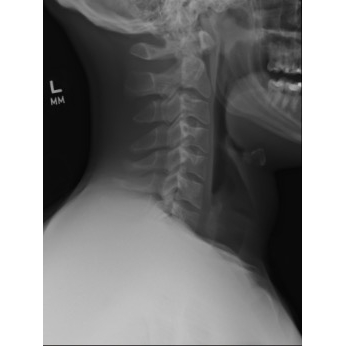

Odynophagia And Dyspnea In A College Basketball Player - Page #3 | |||